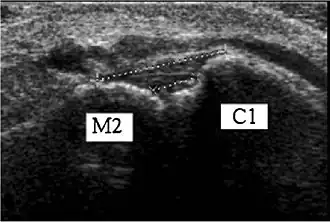

![]() Ultrasonography of the dorsal Lisfranc ligament.[1] | |

The Lisfranc ligament connects the medial cuneiform bone to the second metatarsal.[2] It is a complex of 3 ligaments: the dorsal Lisfranc ligament, the interosseous Lisfranc ligament, and the plantar Lisfranc ligament.[2][3]